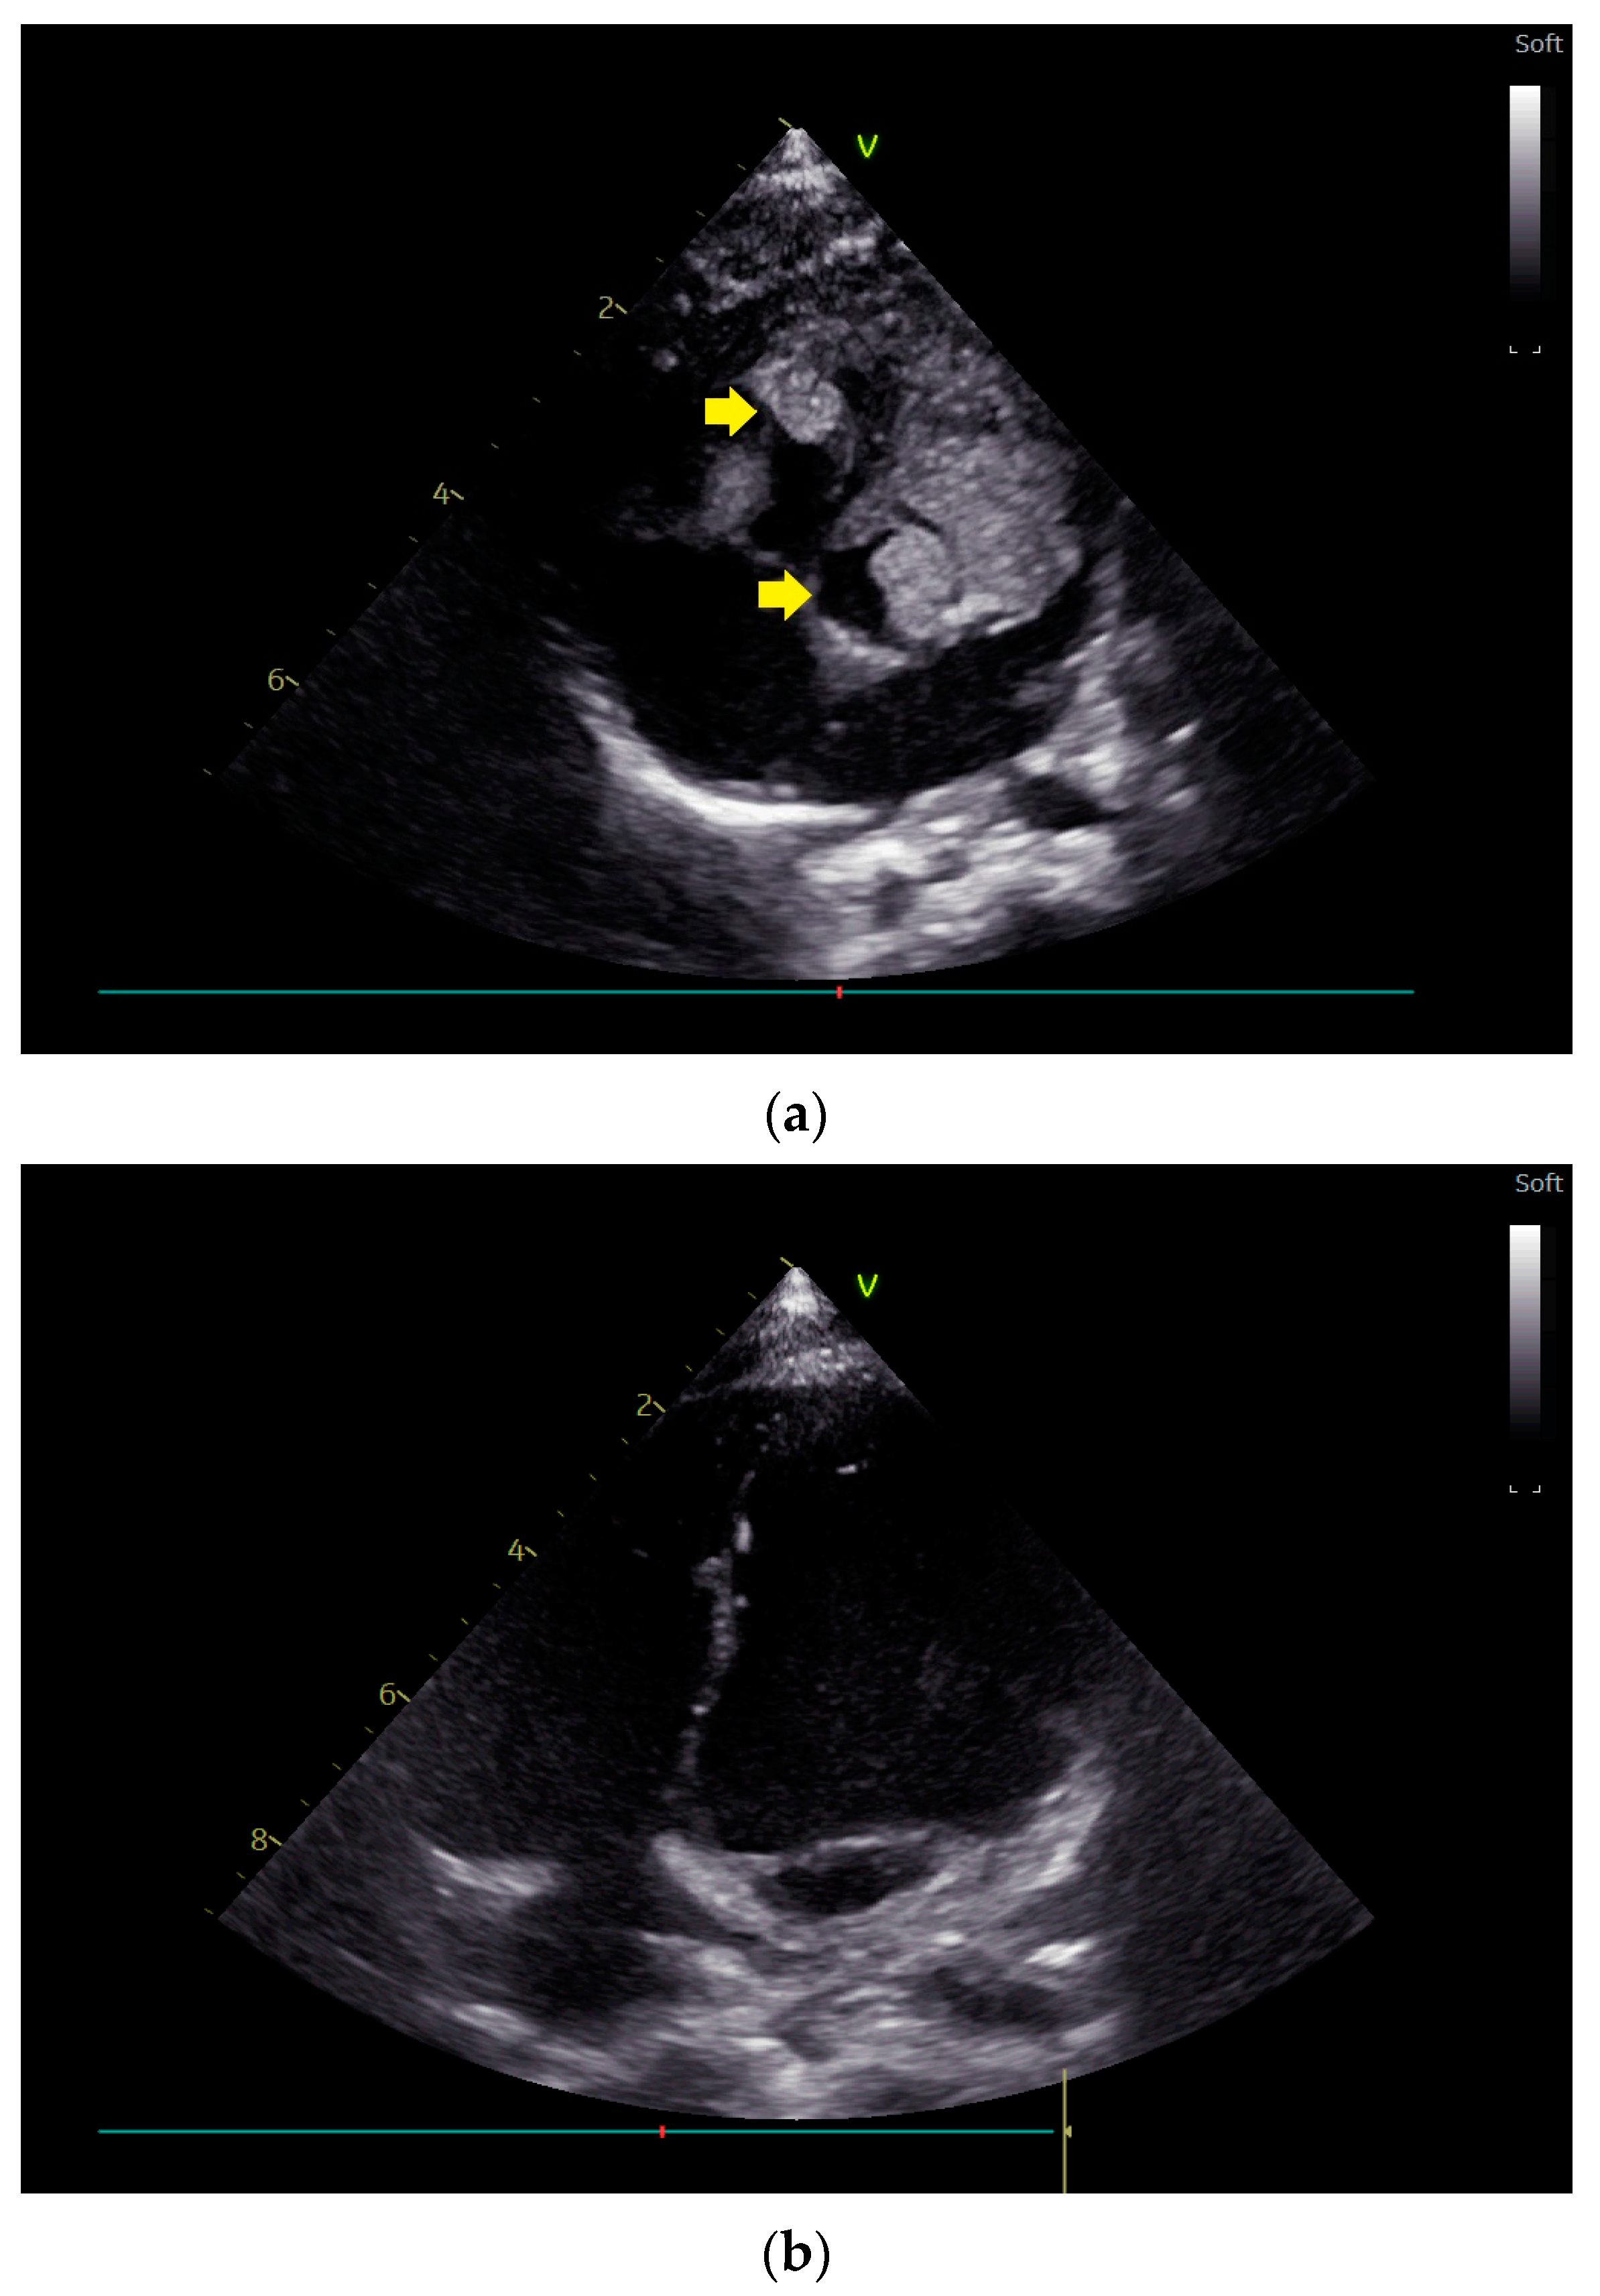

- Fesslova, V.M.E.; Evangelista, M.; Piazza, L.; Saracino, A.; Andronache, A.; Chiarello, C.; Varrica, A.; Giamberti, A.; Frigiola, A. Regression of Cardiac Rhabdomyomas Producing a Severe Aortic Stenosis: Case Report and Discussion of the Literature. Diagnostics 2024, 14, 470. [Google Scholar] [CrossRef]

- Song, E.S.; Jeong, K.; Kim, G.; Hwang, I.J.; Lee, M.J.; Cho, H.J.; Cho, Y.K. Spontaneous Regression of Cardiac Rhabdomyoma Presenting as Severe Left Ventricular Inlet Obstruction in a Neonate with Tuberous Sclerosis. Case Rep. Cardiol. 2018, 2018, 8395260. [Google Scholar] [CrossRef] [PubMed]

- Batmaz, G.; Besikçi, R.; Arslan, G.; Kafadar, I.; Ahunbay, G. Spontaneous regression of huge cardiac rhabdomyoma in an infant. Images Paediatr. Cardiol. 2000, 2, 4–10. [Google Scholar]